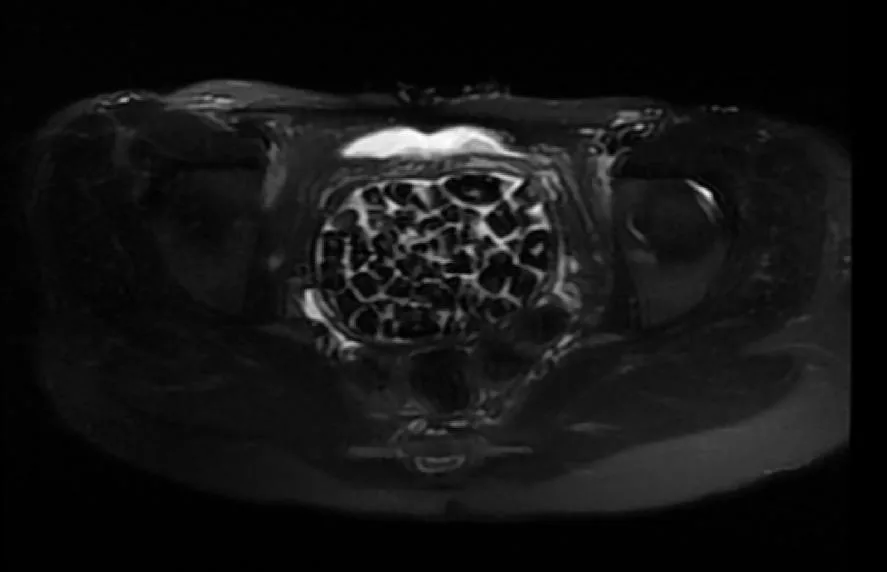

Turkish Doctors Remove 287 Stones From Young Woman

In Türkiye, 21-year-old Fatma Nur Öztürk underwent surgery after severe abdominal pain revealed a rare condition. Doctors discovered and removed 287 stones, the largest measuring 2.5 centimeters, from her bladder and vaginal area.